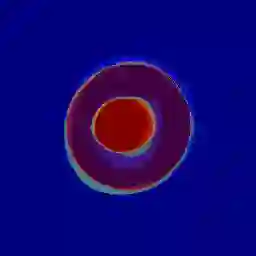

Manual medical image segmentation is subjective and suffers from annotator-related bias, which can be mimicked or amplified by deep learning methods. Recently, researchers have suggested that such bias is the combination of the annotator preference and stochastic error, which are modeled by convolution blocks located after decoder and pixel-wise independent Gaussian distribution, respectively. It is unlikely that convolution blocks can effectively model the varying degrees of preference at the full resolution level. Additionally, the independent pixel-wise Gaussian distribution disregards pixel correlations, leading to a discontinuous boundary. This paper proposes a Transformer-based Annotation Bias-aware (TAB) medical image segmentation model, which tackles the annotator-related bias via modeling annotator preference and stochastic errors. TAB employs the Transformer with learnable queries to extract the different preference-focused features. This enables TAB to produce segmentation with various preferences simultaneously using a single segmentation head. Moreover, TAB takes the multivariant normal distribution assumption that models pixel correlations, and learns the annotation distribution to disentangle the stochastic error. We evaluated our TAB on an OD/OC segmentation benchmark annotated by six annotators. Our results suggest that TAB outperforms existing medical image segmentation models which take into account the annotator-related bias.